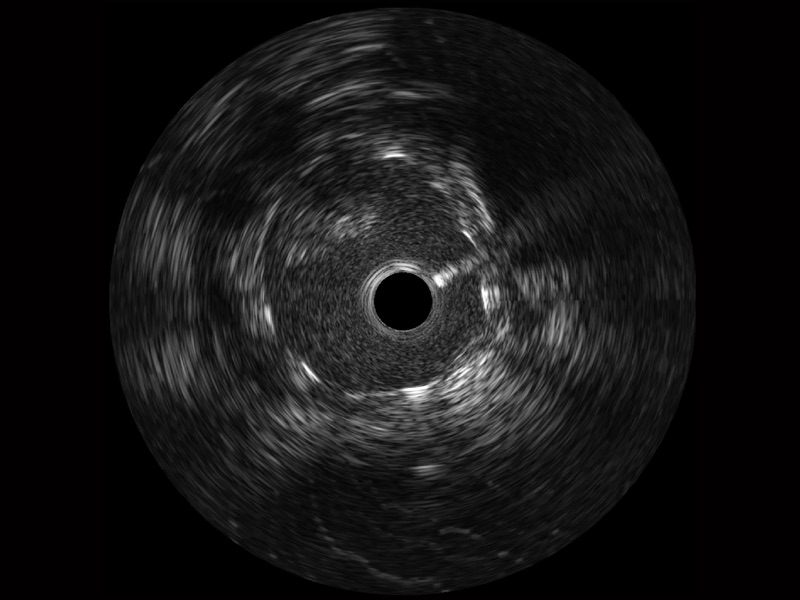

• 传统IVUS图像

对比传统IVUS导管成像,亚星官网宽频IVUS图像的近场支架梁显影更细腻,远场中膜外血管仍清晰可辨,兼顾远中近,兼顾分辨力与穿透深度